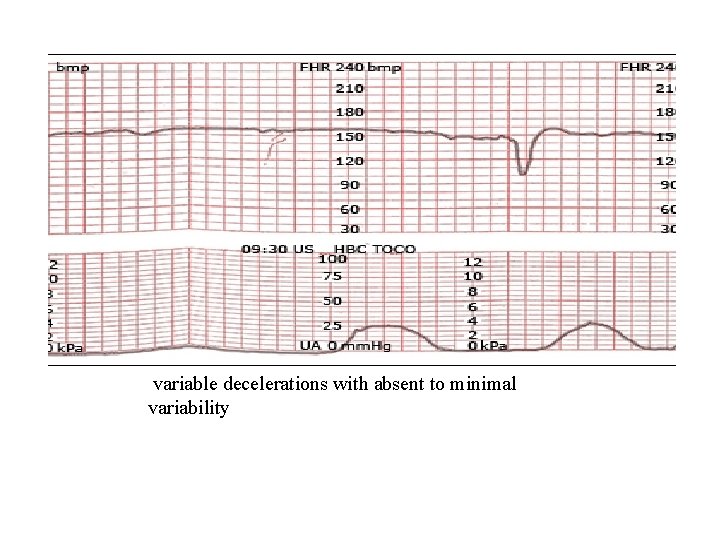

variable decelerations with absent to minimal variability

Variable decelerations with minimal to absent variability

Category III tracings are predictive of abnormal fetal acid -base status at the time of observation. (1) Absent baseline FHR variability and any of the following: • Recurrent late decelerations • Recurrent variable decelerations • Bradycardia (2) Sinusoidal pattern

Category III • Category III tracings are predictive of abnormal fetal acid-base status at the time of observation. Prompt evaluation is indicated and most parturients will require expeditious intervention, such as provision of supplemental oxygen, change in position, treatment of hypotension, and discontinuation of any uterotonic drugs being administered